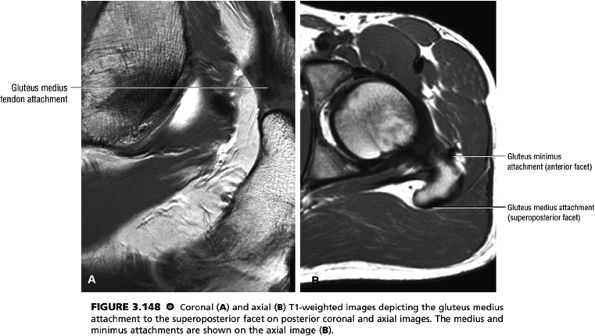

FIGURE 3.16 ● GLUTEUS MEDIUS The gluteus medius abducts and medially rotates the thigh when the extremity is extended.

FIGURE 3.17 ● GLUTEUS MINUMUS The gluteus minimus abducts and medially rotates the thigh when the extremity is extended.